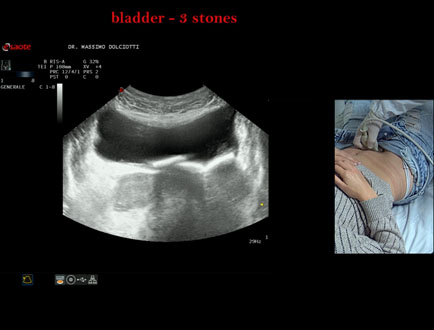

Data inserimento: 21/10/2025

Ecografia del: 15/10/2025

Strumento: Esaote MyLab Eight

Sonda: Convex Multifrequenza 1-8 MHz

Età Paziente: F 45 anni

Motivazione dell'esame: da alcuni mesi, disuria ed infezioni urinarie recidivanti.

Commento all'esame: le immagini ed il video documentano 3 immagini iperecogene, con cono d'ombra posteriore, da ricondurre a litiasi multipla della vescica.

Conclusioni: 3 calcoli della vescica (3 bladder stones).

Presentazione: Dr. Massimo Dolciotti - Ancona

Elaborazione digitale: Andrea Dini - Ancona